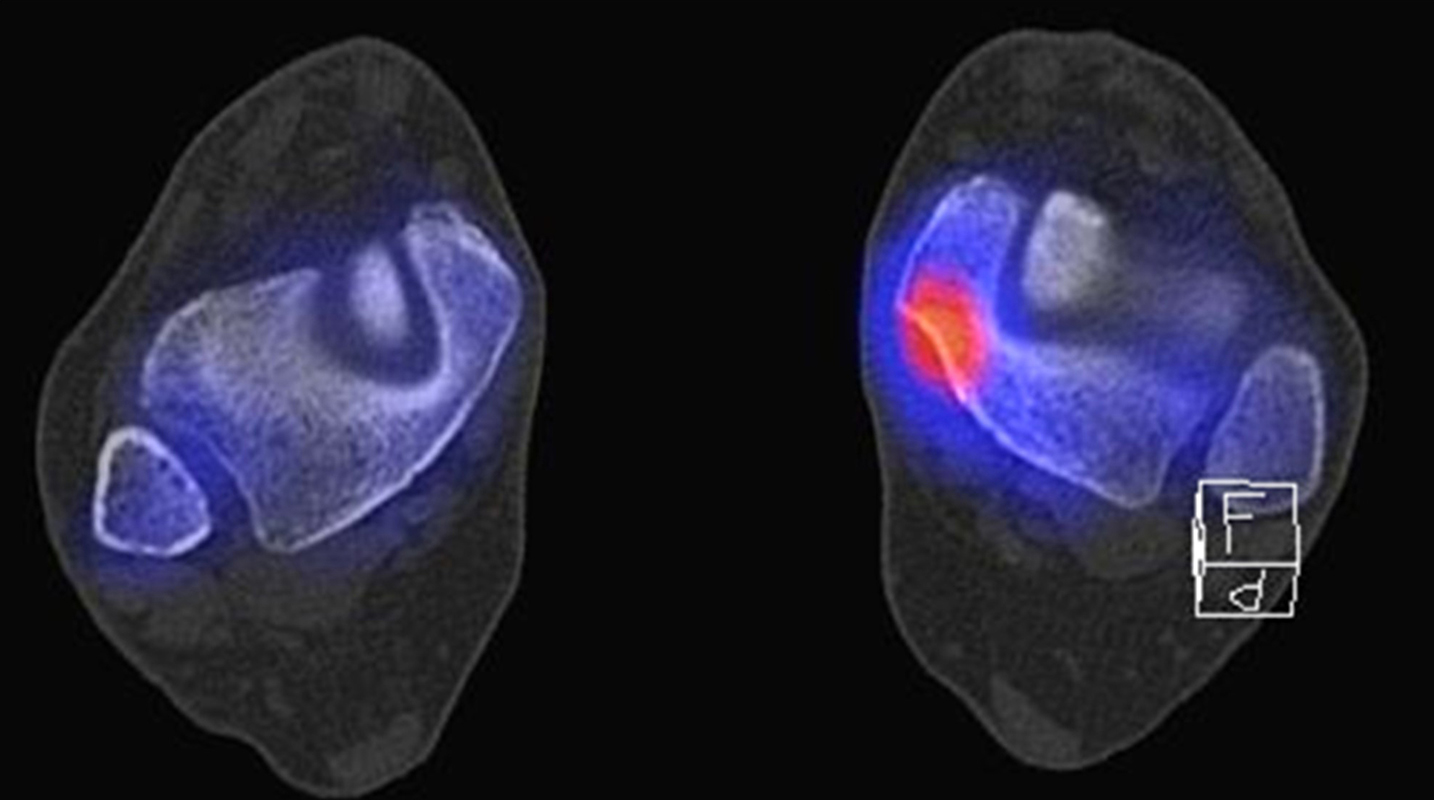

Abbildung 1.8.a und b: Akute Arthritis bei bekannter Gicht in beiden OSG: links die Früh-/Weichteilphase; rechts die Mineralisations­phase. Deutliche, entzündlich bedingte Mehranreicherungen in der Früh-/Weichteilphase. In der Mineralisation­sphase erkennt man die entzündliche Mitreaktion der subchondralen Gelenkabschnitte.

Abbildung 1.8.c - e: Akute Arthritis in beiden OSG, rechts > links. Im SPECT/CT erkennt man die Mitreaktion der subchondralen Gelenkabschnitte. Die Arthritis ist so akut, dass (noch) keine ossären morphologischen Veränderungen im CT abgrenzbar sind.